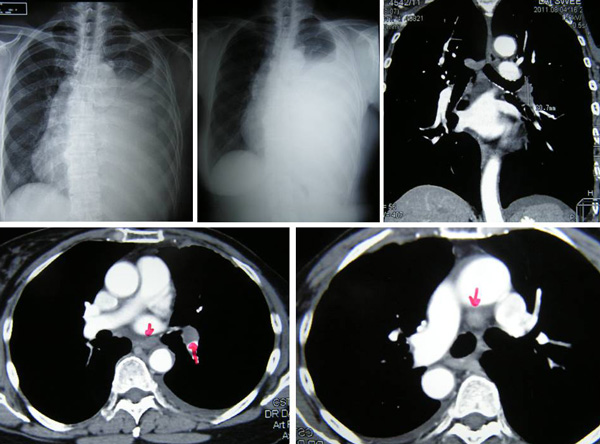

SH said she was well all these years and her progress was monitored by her doctor. About 10 years later, in early 2009, SH developed shortness of breath. She could not lift her left arm. She was tired and lost her appetite. A chest X-ray indicated large left pleural effusion. SH had the fluid in her lung tapped out. A CT scan on 7 January 2009 indicated several subcentimeter nodules in her left lung. The lymph nodes in the left axilla and aortopulmonary window were enlarged. Impression: left pulmonary and pleural metastasis.

SH sought a second opinion from another oncologist at a university hospital. Another CT scan was performed and it also confirmed a metastatic breast cancer with left pleural effusion with small benign liver cysts.

A bone scan done on 29 January 2009 indicated multiple skeletal metastases in the sternum and two ribs on the left side.

In August 2011 SH developed shortness of breath again. A CT scan on 4 August 2011 confirmed presence of mild left pleural effusion. Fluid was tapped out of her lung again.